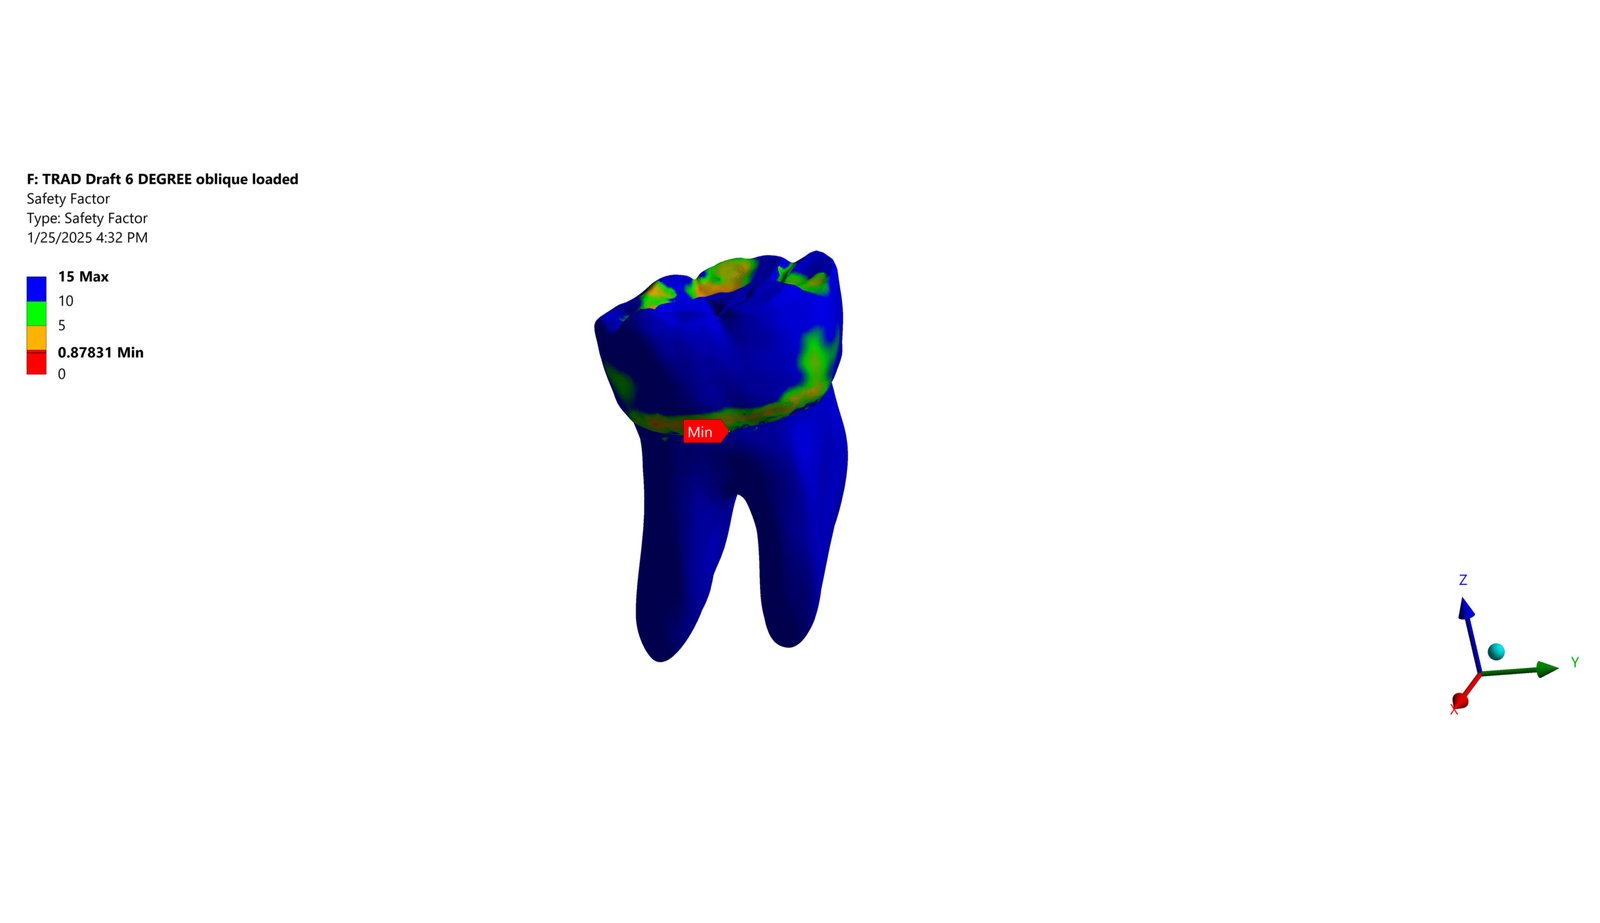

The Endodontic FEA section evaluates the biomechanical performance of root canal–treated teeth, endodontic tools, and reinforcement strategies. Through precise material characterization and micro-CT–based superimposition, we assess fracture risk, stress pathways, and instrument fatigue under various clinical scenarios. These simulations guide the selection of safer instrumentation techniques and restorative strategies. Our goal is to enhance predictability and reduce procedural complications.